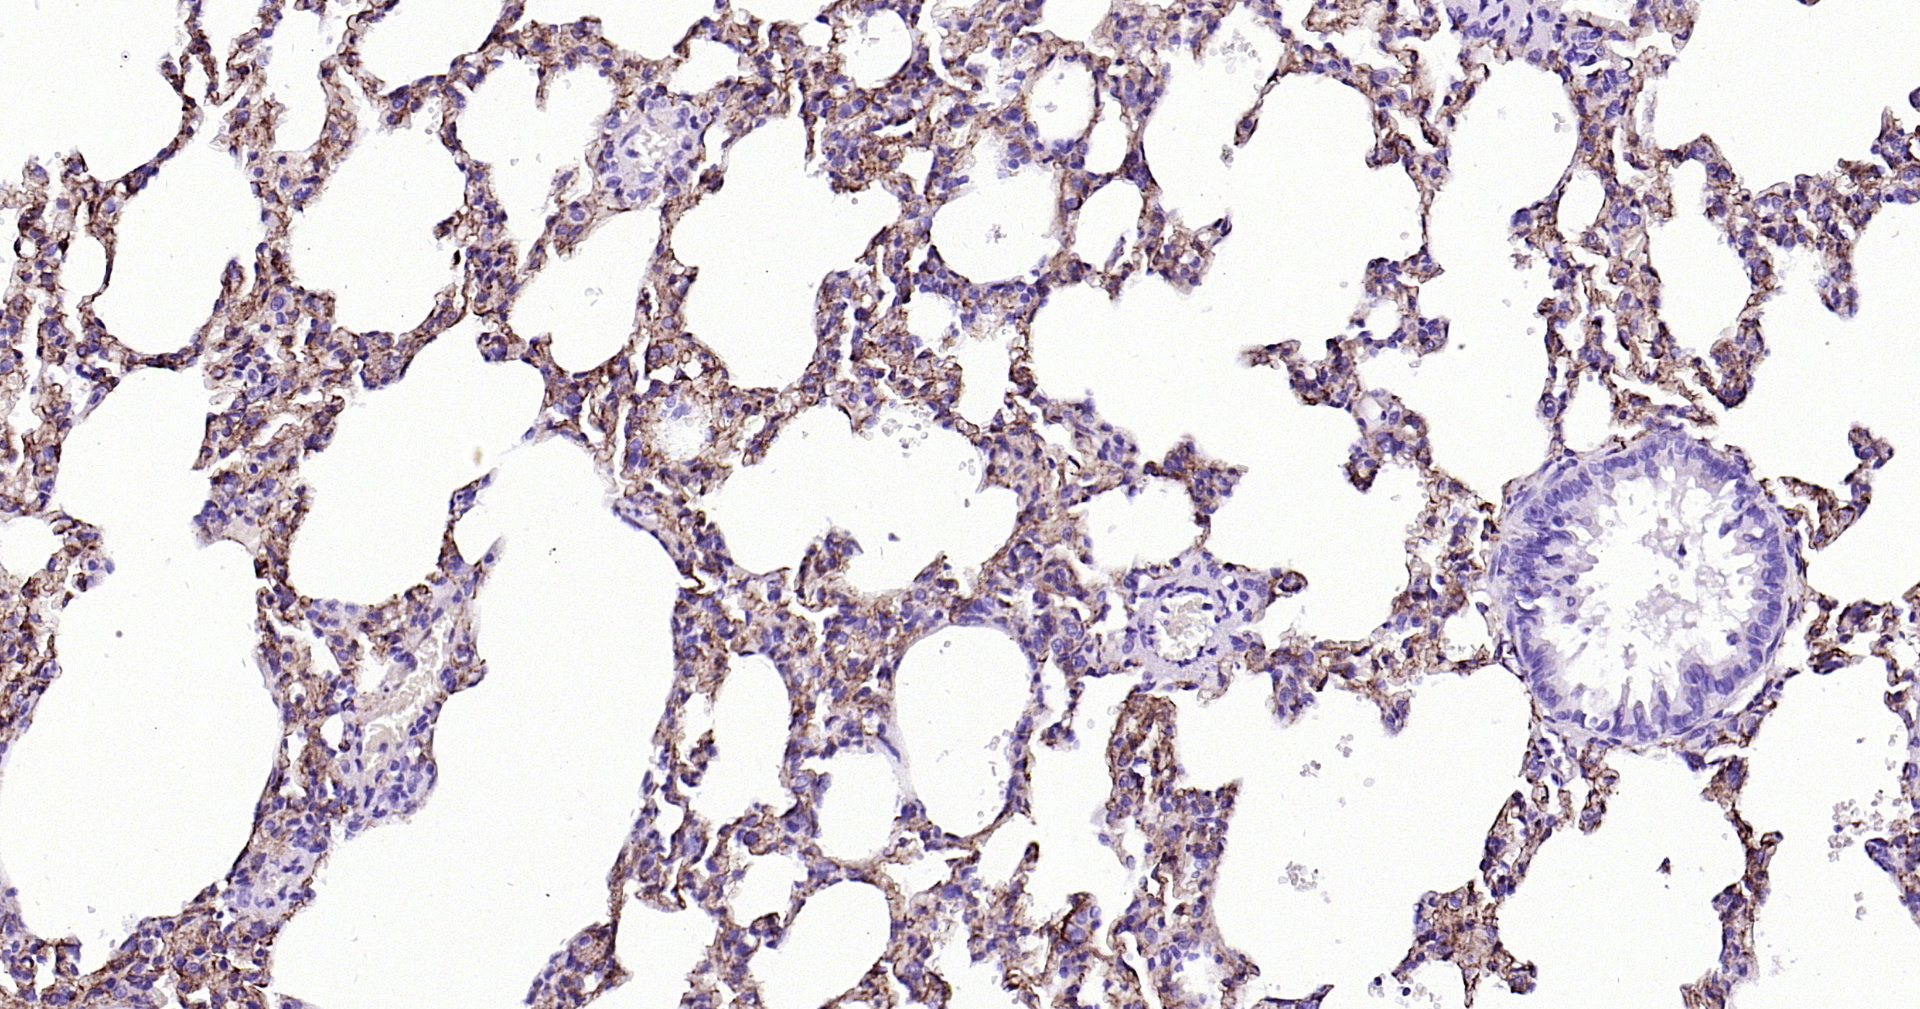

Applications IHC-P, IHC-F, IF(IHC-P)

IHC-P 1:200-1000